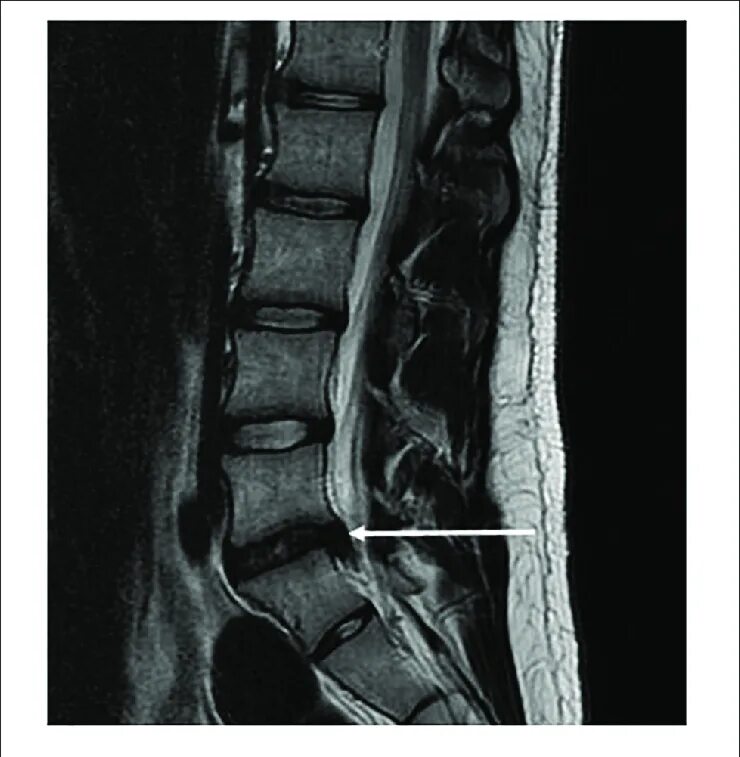

Грыжа диска на уровне l5 s1